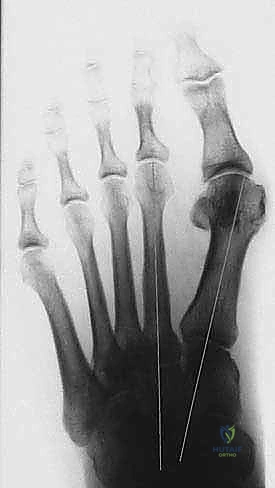

- التصوير بالأشعة السينية (X-rays) أثناء الوقوف: هذا أمر بالغ الأهمية. الأشعة والوزن محمل على القدم تظهر الدرجة الحقيقية للتشوه.

يقوم الدكتور هطيف بقياس زوايا محددة:

* زاوية إبهام القدم الأروح (HVA): الزاوية بين عظم المشط الأول والإصبع الكبير.

* الزاوية بين الأمشاط (IMA): الزاوية بين عظم المشط الأول والثاني.

بناءً على هذه الزوايا، يتم تصنيف الحالة إلى خفيفة، متوسطة، أو شديدة. جراحة (ماو) تُخصص عادة للحالات المتوسطة إلى الشديدة التي تتطلب تصحيحاً كبيراً ومستقراً.

سُميت تقنية ماو (Mau) بهذا الاسم نسبة إلى الجراح الذي وصفها، وهي عبارة عن قطع عظمي (Osteotomy) في جسم عظم المشط الأول. ما يميز هذه التقنية ويجعلها فريدة وقوية هو هندسة القطع الجراحي.

يتم إجراء القطع العظمي بشكل مائل، بدءاً من السطح الأخمصي القريب (Plantar-proximal) إلى السطح الظهري البعيد (Dorsal-distal). هذا الاتجاه المائل للقطع يوفر استقراراً ميكانيكياً هائلاً ضد قوى الإزاحة التي تحدث أثناء تحمل الوزن والمشي.

- تصحيح الزوايا الكبيرة: تتيح هذه التقنية تحريك العظم بمسافة كبيرة لتصحيح زاوية (IMA) الواسعة جداً.